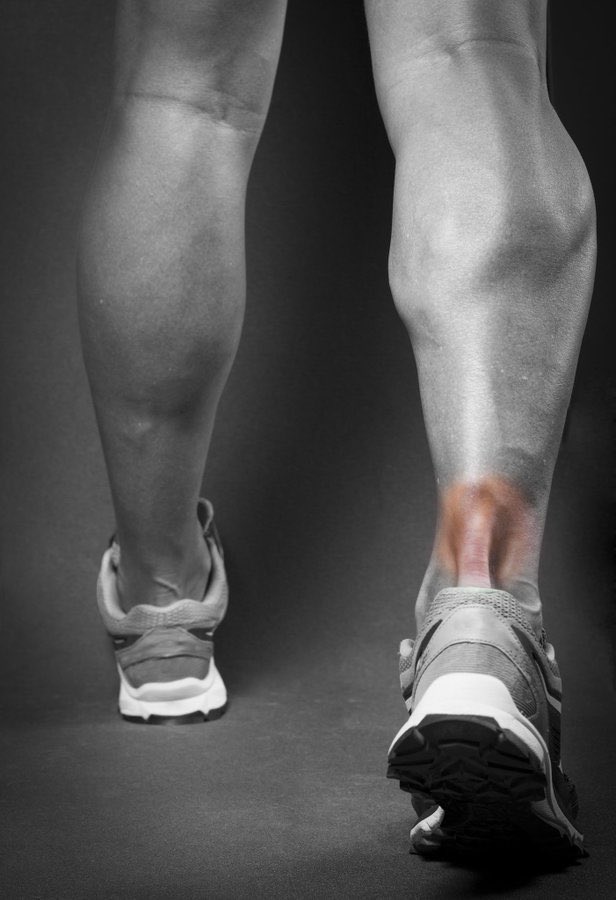

يحدث التهاب او تمزق #الوتر_العرقوبي

نتيجة

♦️الاستخدام المفرط لوتر العرقوب

♦️في العدائين الرياضين نتيجة التحميل الزائد

♦️لدى الأشخاص الذين يمارسون الرياضية فقط في عطلة نهاية الأسبوع

♦️#السمنة و تفلطح القدم تزيد من الخطورة

♦️بعض الادوية مثل الفلوروكينولونات

أعراض التهاب #الوتر_العرقوبي

🔻يبدأ الألم المصاحب على هيئة وجع خفيف في الجانب الخلفي للساق أو أعلى الكعب بعد ممارسة النشاط الرياضي

🔻قد تحدث نوبات ينتج عنها الشعور بألم أكثر شدة بعد الجري أو صعود السلالم

🔻وجع أو تيبس خاصة في الصباح، والذي عادة ما يتحسن مع اليوم بعد الحركة